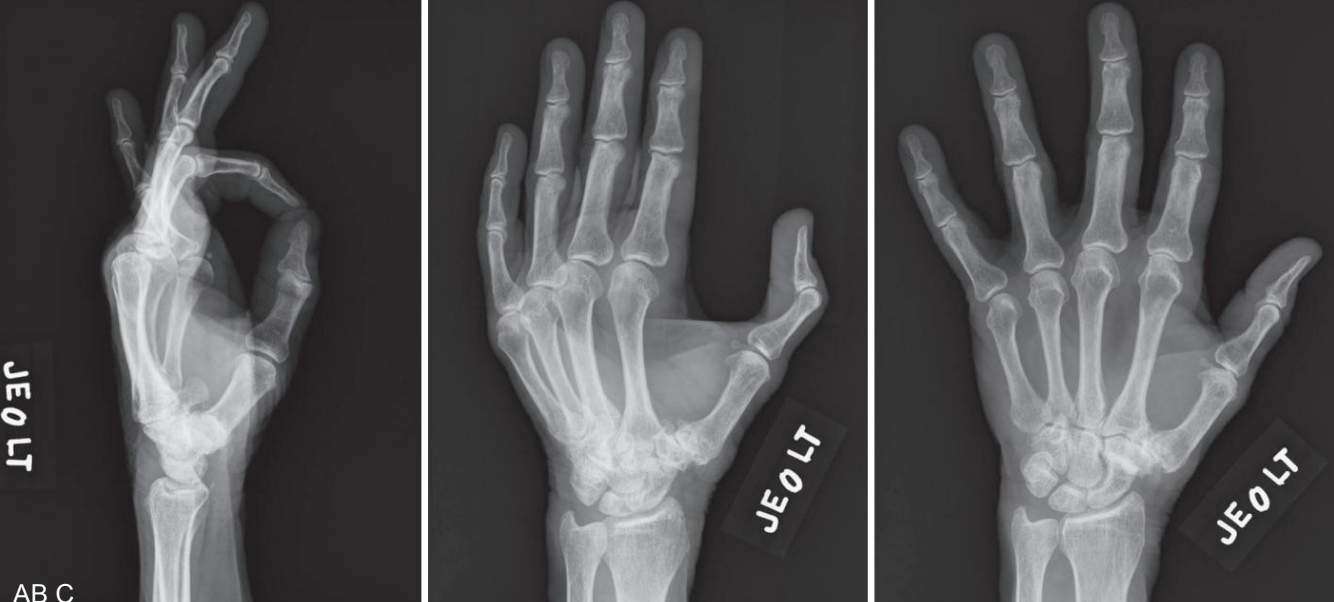

A radiografia é utilizada para confirmar o diagnóstico e avaliar o estágio da doença. As incidências mais usadas incluem PA, perfil e oblíqua da mão, além da incidência de Robert, que permite uma visualização mais precisa da articulação .